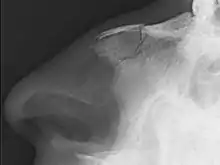

Plain X-ray showing a nasal fracture

Diagnostic methodTypically based on symptoms, occasionally plain X rays[1]

Nasal fractures are usually identified visually and through physical examination.[1] In addition, relevant questions to ask the patient include whether there is a noticeable cosmetic deformity and whether the patient has difficulty breathing through the nose after the injury. Medical imaging is generally not recommended.[1][3] A priority is to distinguish simple fractures limited to the nasal bones (Type 1) from fractures that also involve other facial bones and/or the nasal septum (Types 2 and 3). In simple Type 1 fractures X-Rays supply surprisingly little information beyond clinical examination. However, diagnosis may be confirmed with X-rays or CT scans, and these are required if other facial injuries are suspected.[3]